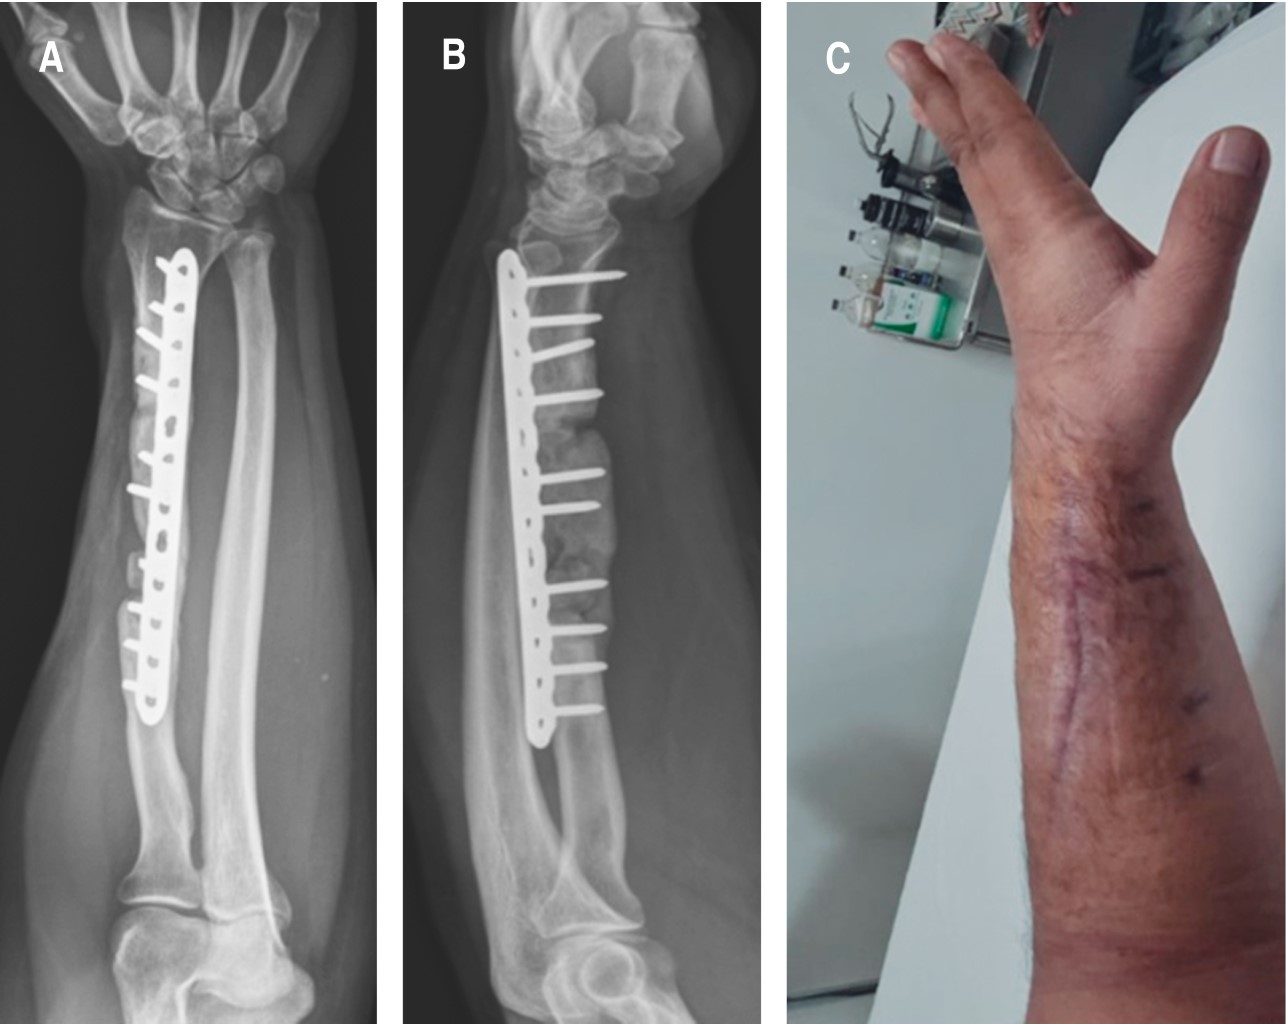

Después de 16 semanas de seguimiento con normalización de cuenta leucocitaria (< 4,000 mm3) y reactantes de fase aguda negativos (VSG < 10 mm/h, PCR < 5 mm mg/l), que traducen infección remitida, se decide realizar Masquelet fase 2. Primero posicionamos al paciente en decúbito lateral, y con ayuda de control fluoroscópico se posiciona una aguja Jamshidi 11 G x 10 cm en la cresta iliaca posterosuperior en la sección anatómica del íleon 6, además, de manera percutánea se procede a realizar aspirado de médula ósea, del que se extrae 1 ml, al girar el bisel y retraer la aguja por cada mililitro de aspirado, con lo cual se evita aspirar cantidades mayores a éste, debido a la dilución por sangre periférica que disminuye la concentración de células madre mesenquimales (MSC, por sus siglas en inglés), hasta tener tres jeringas de 10 ml.11-13 En el transoperatorio, al hacer escarificación y hueso sangrante, se determina una pérdida ósea de 7 cm, realizamos toma y aplicación de dos bloques de cresta iliaca de 2 y 5 cm, respectivamente, y colocamos LCP de 3.5 de radio con 12 orificios, se colocaron cuatro tornillos proximales, dos al injerto y cuatro distales, con lo que nos aseguramos de obtener una osteosíntesis lo más rígida posible. El injerto restante se prepara en pequeños fragmentos de 3 mm. Finalmente, se procede a realizar mezcla del aspirado de médula ósea con el aloinjerto óseo de cresta, con el cual se rellenó la pérdida restante (Figura 3).